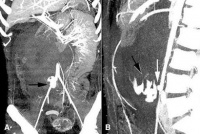

S35.4 Травма на бъбречните кръвоносни съдове

Травма на бъбречните кръвоносни съдове обхваща 16% от всички коремни съдови наранявания. 1,3 - 1,6 п...